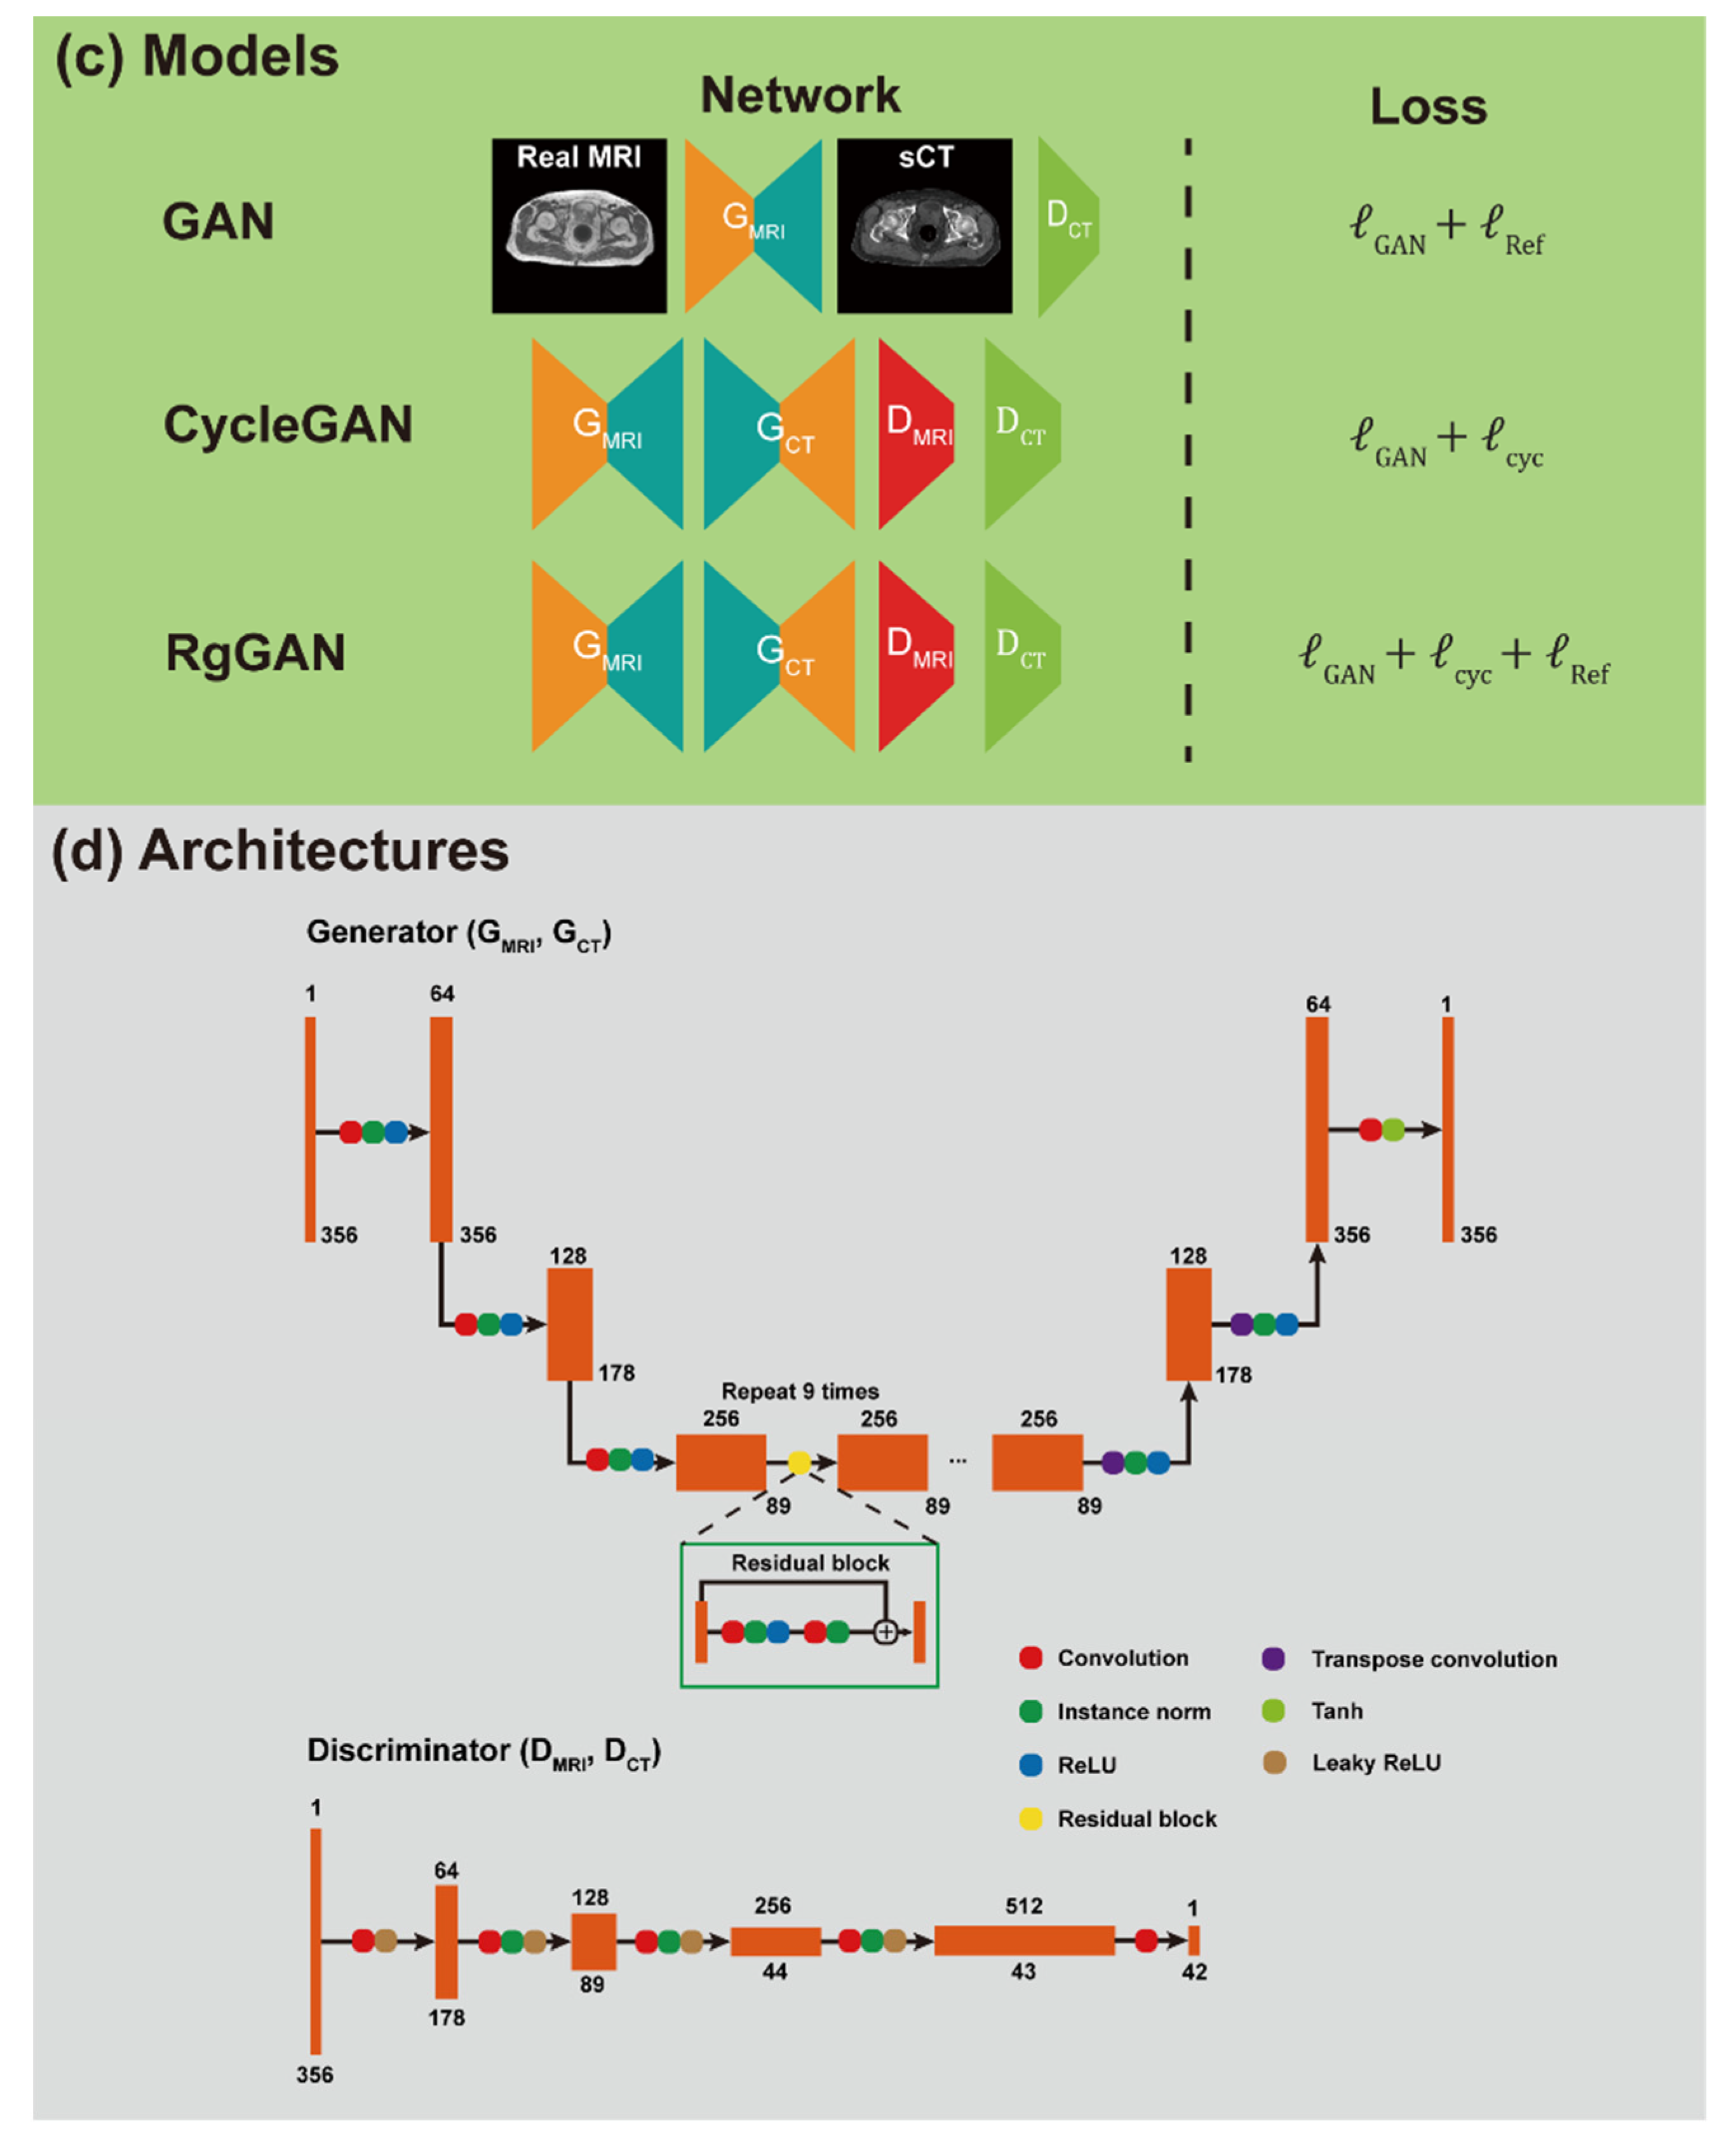

3.2. Image Quality

3.3. Dosimetric Comparison